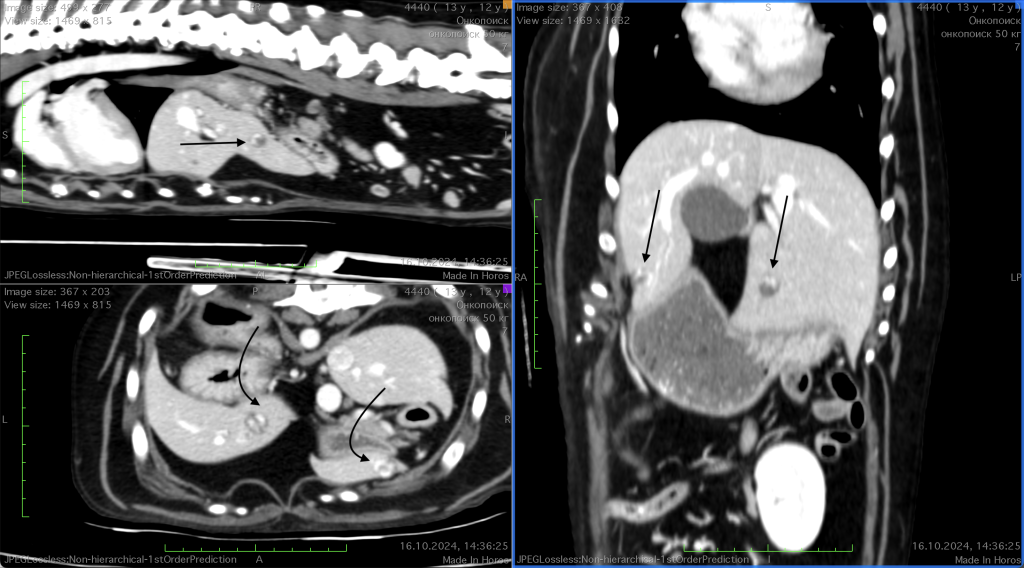

Анамнез и диагностика. У собаки (метис, 10 лет, интактный кобель) в ходе планового обследования во время проведения УЗИ было выявлено бессимптомное новообразование селезенки. При динамическом наблюдении за состоянием пациента в течение месяца был зафиксирован выраженный рост новообразования. В связи с этим 03.08.2024 было принято решение о проведении компьютерно-томографического исследования с ангиографией. Исследование подтвердило наличие новообразования селезенки, характеризующегося гетерогенным накоплением контраста (фото 1.1), а также множественных гиперваскуляризированных участков в тканях селезенки. На основании полученных данных было принято решение о выполнении спленэктомии по стандартной методике.17.08.2024 после получения гистологического заключения, подтверждающего диагноз «гемангиосаркома селезенки», была проведена контрольная компьютерная томография. На данном этапе исследования в печени были обнаружены единичные очаги, подозрительные в отношении метастатических очагов (фото 1.2).

- 16.09.2024 после клинического улучшения состояния пациента была проведена контрольная КТ, которая показала отсутствие прогрессирования метастатических очагов в печени на фоне прекращения лечения (рис. 2, 3).